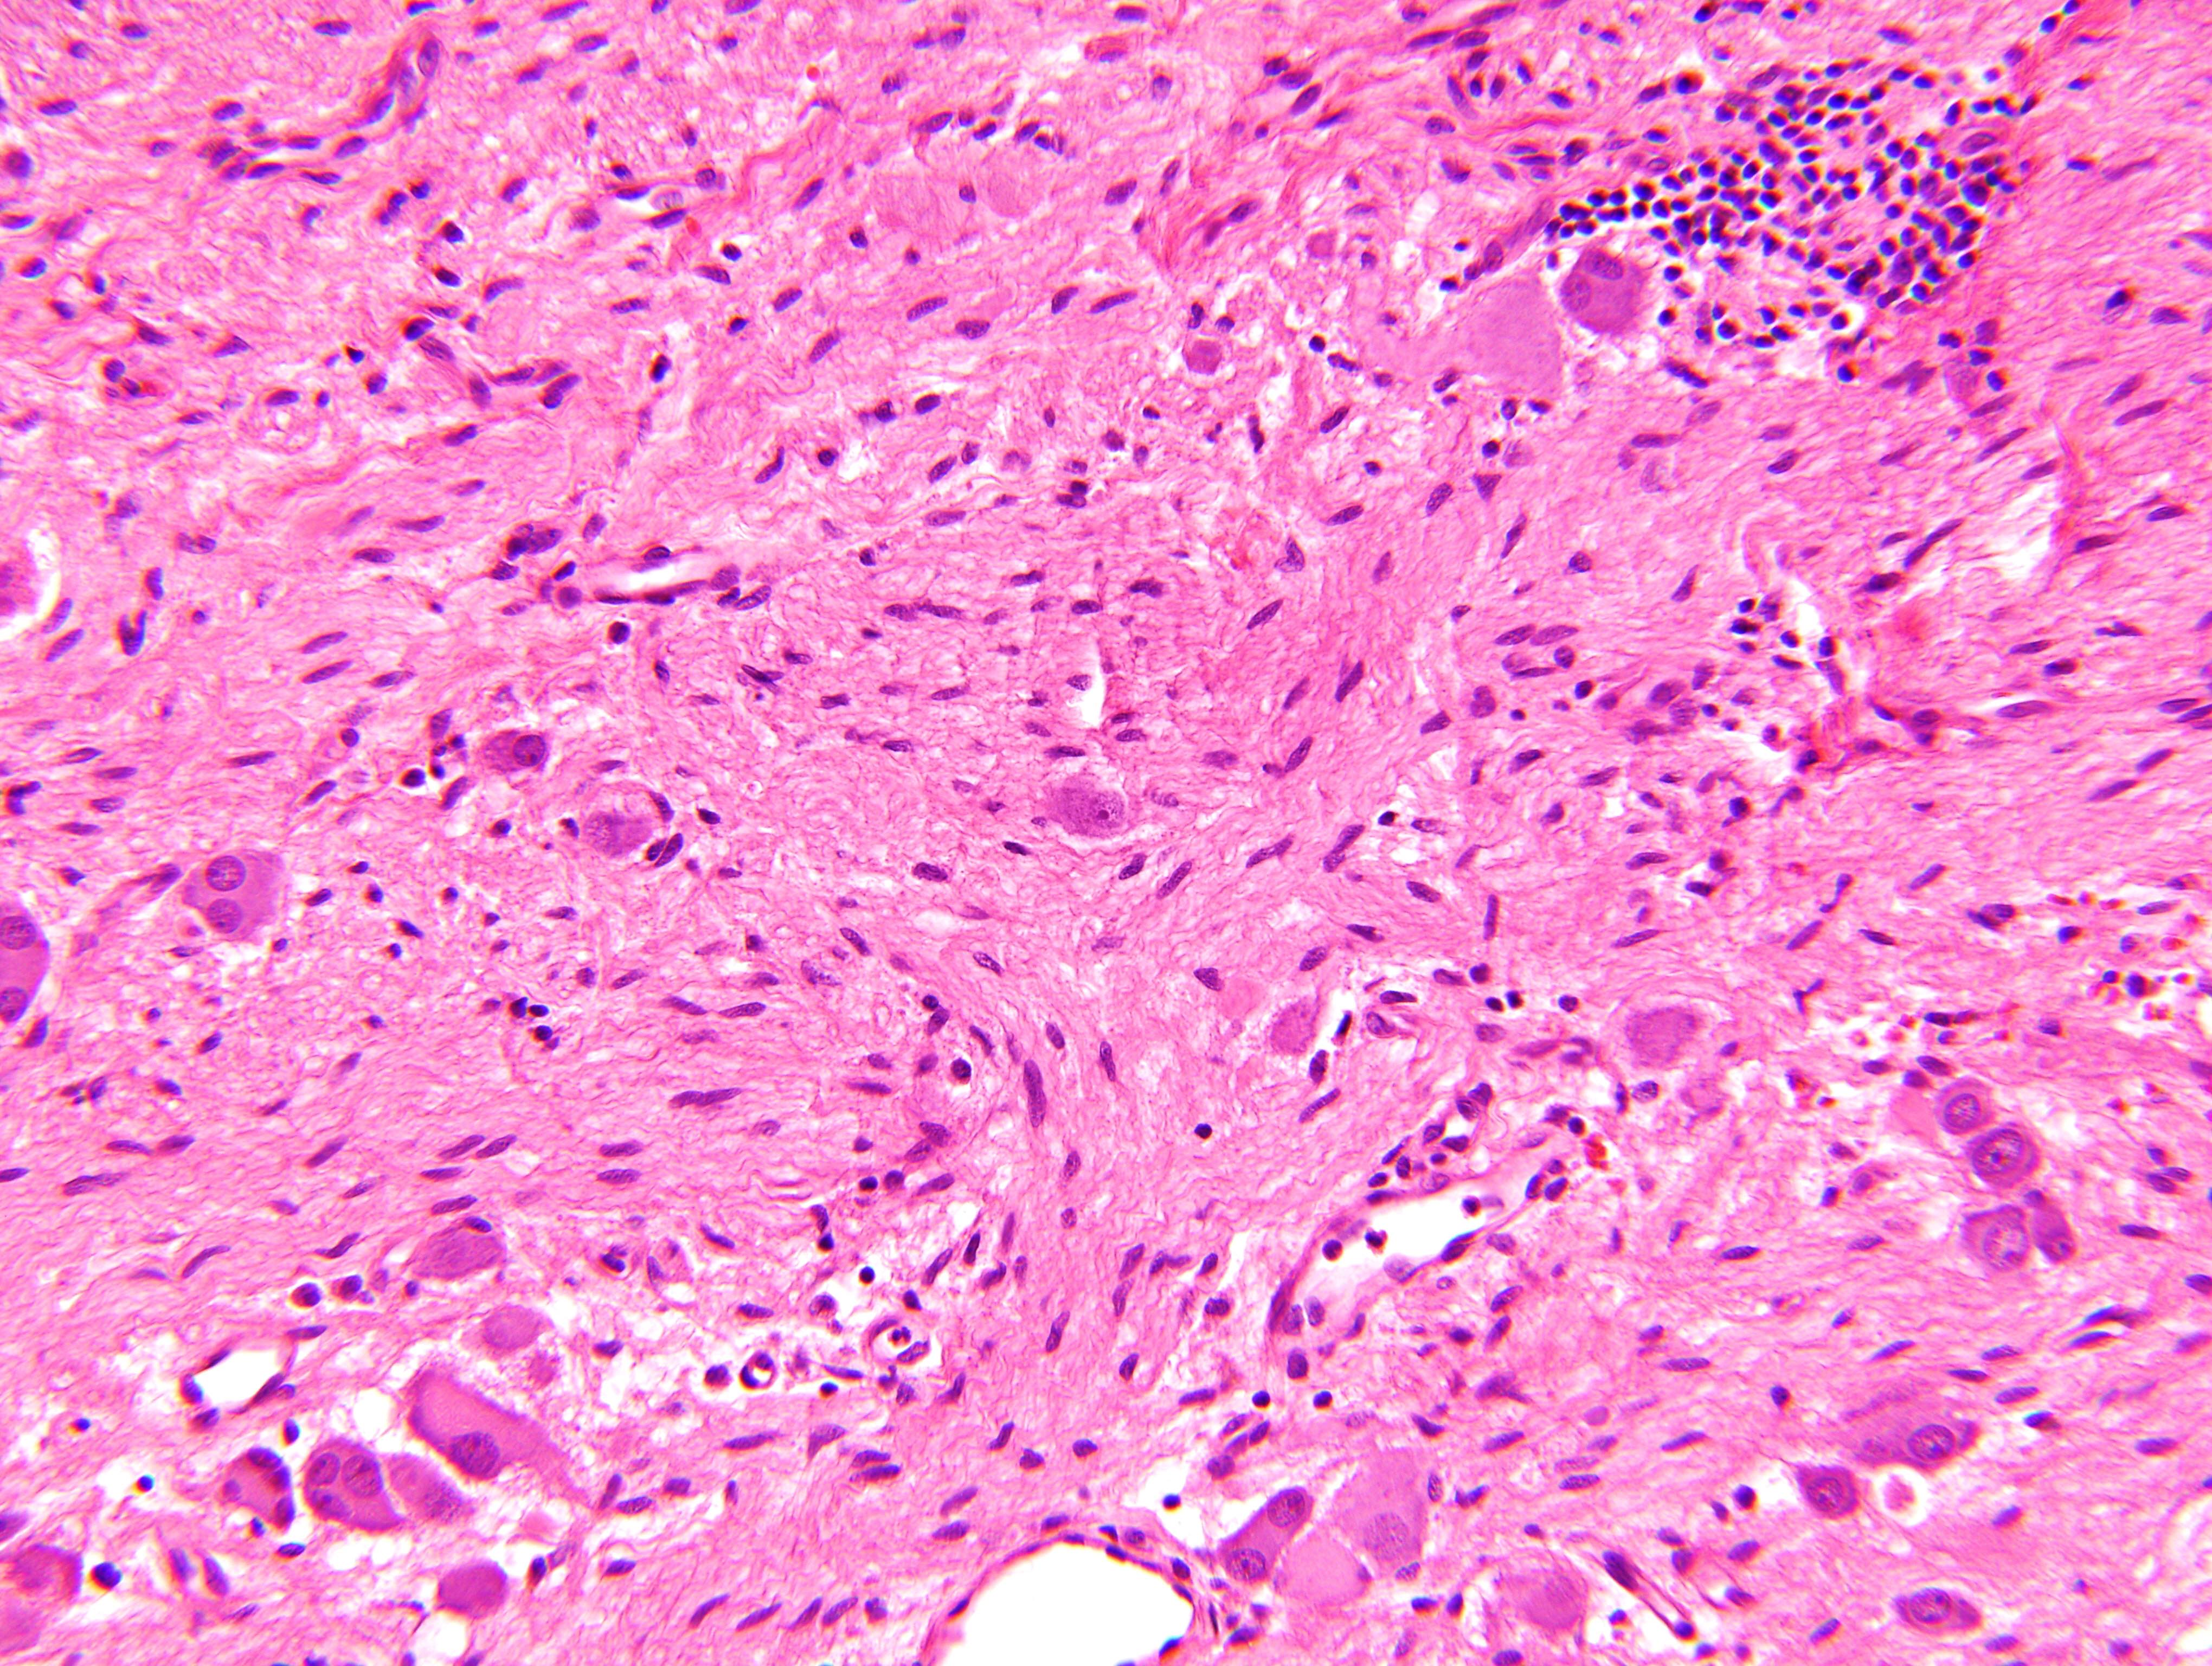

Microscopic (histologic) description

- Architecture: lobular, diffuse / solid, organoid

- Neuroblasts

- Homer Wright pseudorosettes = circular, ovoid, angular zones of pale staining neuritic cell processes surrounded by tumor cell nuclei; may rarely palisade

- Minimal cytoplasm, may have cytoplasmic tail

- Round to ovoid nuclei with stippled salt and pepper chromatin, inconspicuous nucleoli

- Ganglion cells

- Abundant granular eosinophilic cytoplasm (Nissl substance = rough endoplasmic reticulum)

- Distinct cell borders

- Nuclear enlargement, eccentric nuclei, prominent nucleoli

- May see neuromelanin pigment (brown, finely granular; rarely present), cystic degeneration, hemorrhage, dystrophic calcification

Microscopic (histologic) images

Contributed by Carmen Perrino, M.D. and Debra L. Zynger, M.D.

Intermixed type

Nodular type